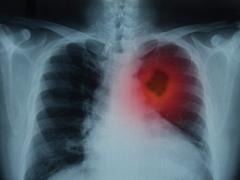

Cancer